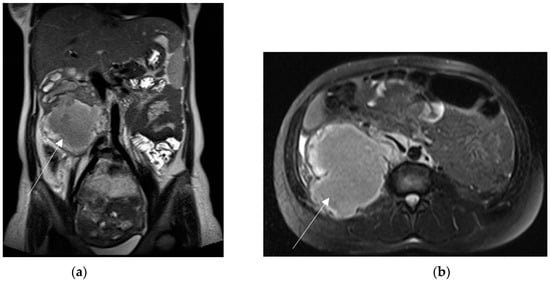

Liver infarction can be undetectable through US or appear as peripheral geographic hypoechoic bands [43]. MRI can show corresponding parenchymal signal changes, such as hyperintense on T2WI and hypointense on T1WI, according to the degree of the necrosis [44]. CT shows peripheral, ill-defined and wedge-shaped areas of decreased or absent enhancement, without mass effect (Figure 4); enhanced intrahepatic vessels are visible within the ischemic areas [42,45].

Figure 4.

HELLP syndrome in a 29-year-old patient with severe abdominal pain, onset 72 h after delivery. Prepartum hypertension, proteinuria and derangement of LFTs. Coronal and axial contrast-enhanced CT (a,b) show large and markedly hypoattenuating intrahepatic areas consistent with liver infarction (arrows). Lack of active arterial hemorrhage or intrabdominal bleeding.